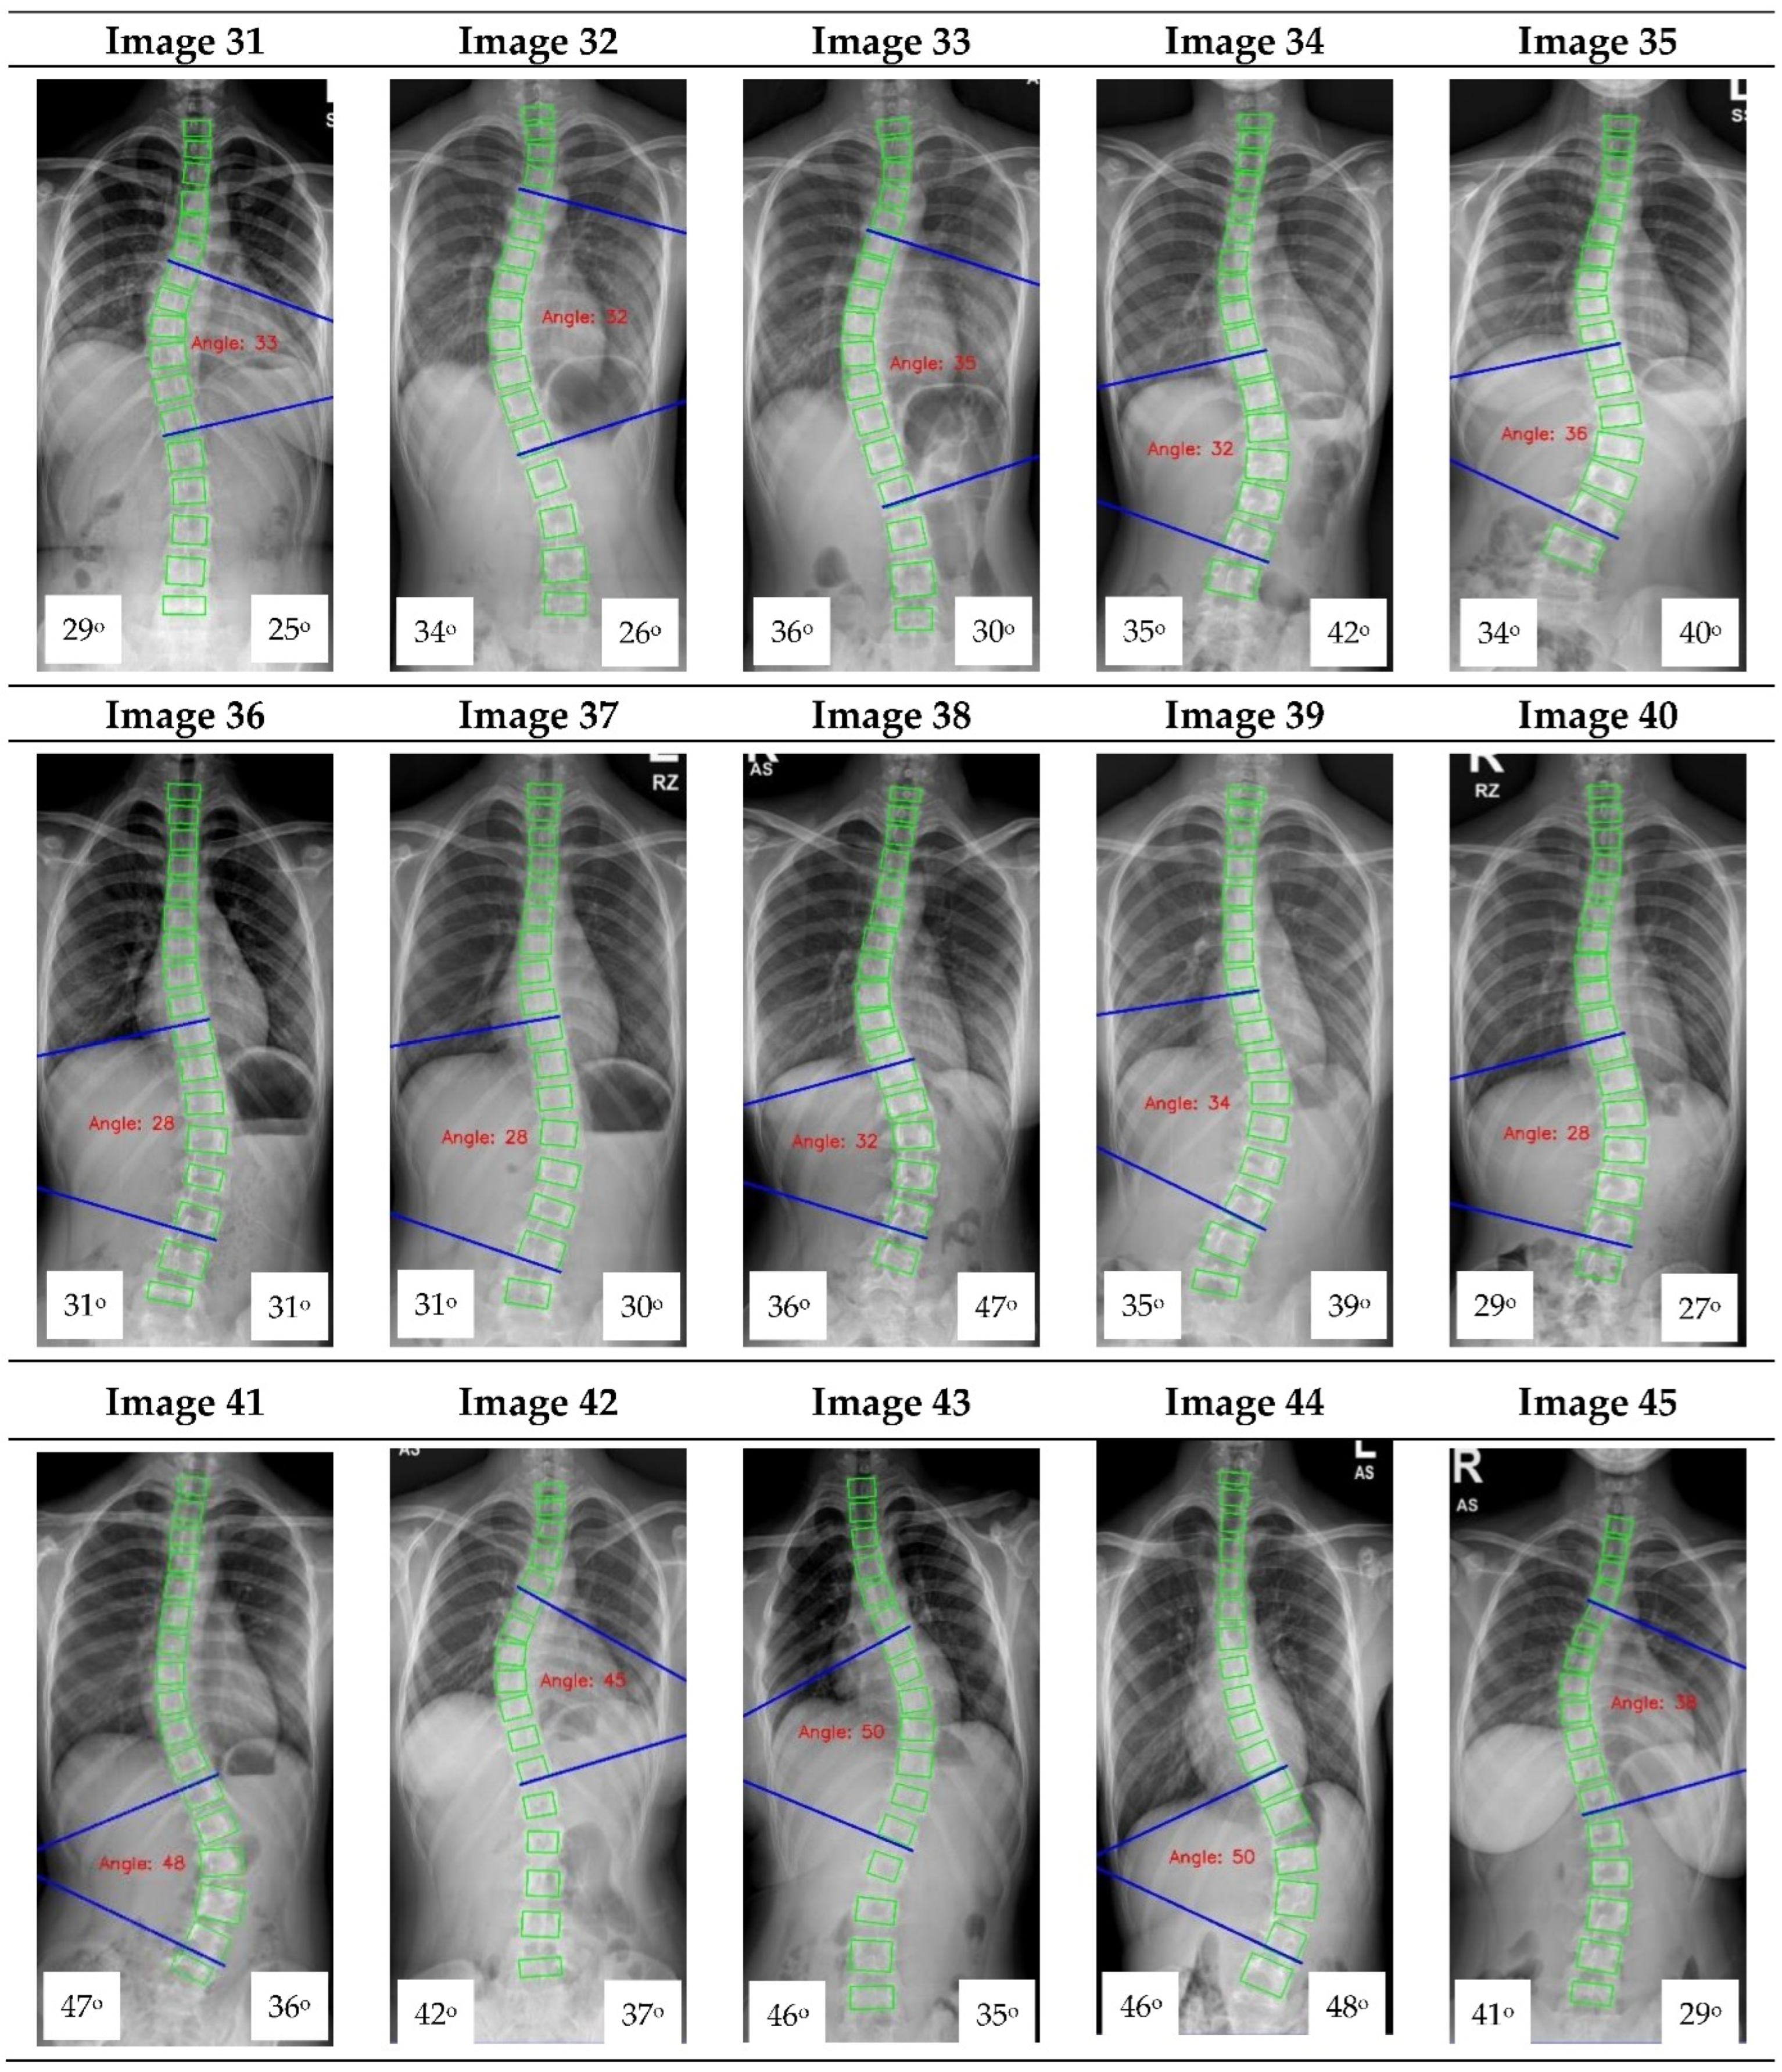

Appendix A. CNN Cobb Angle (CA) Measurement of X-ray Images

Figure A1.

The red font inside the X-ray image is a CNN CA measurement. Observer 1 and 2 evaluation is presented on the bottom left and right, respectively.